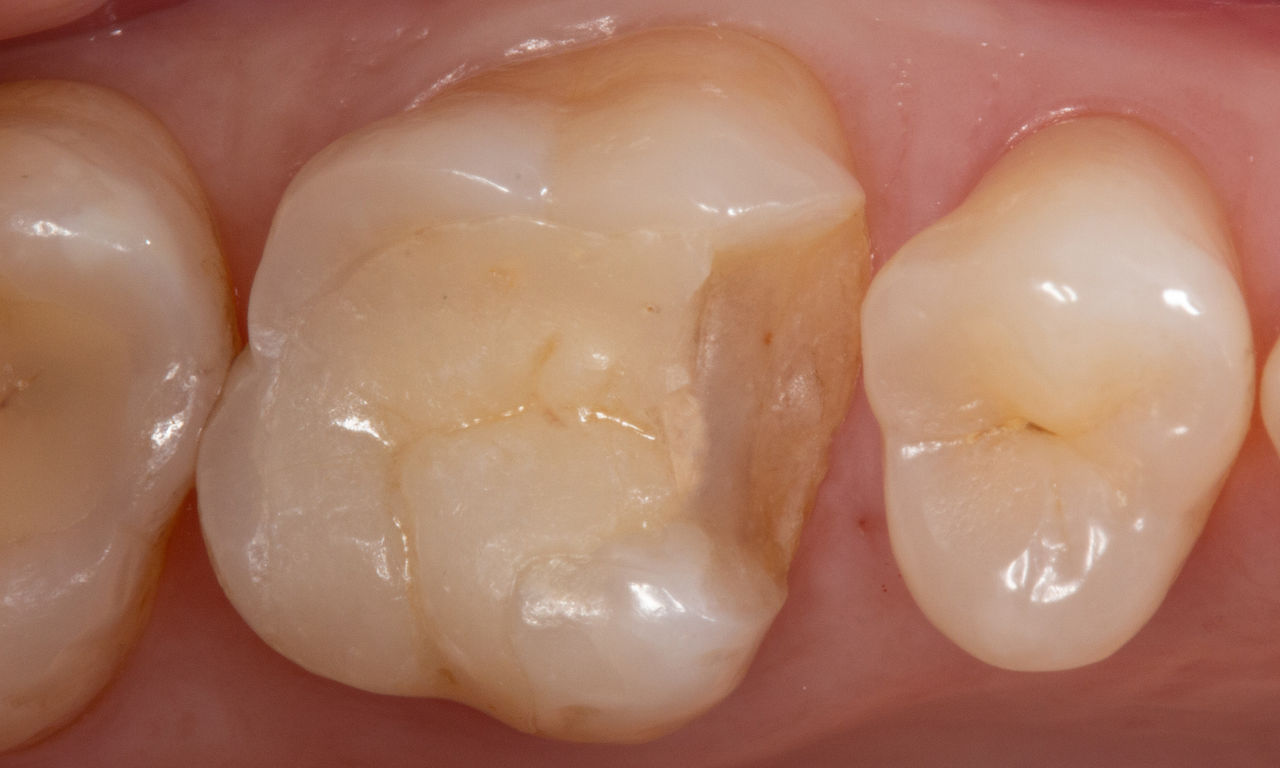

Restauration de la deuxième molaire mandibulaire en consultation

Couronne partielle CEREC Tessera

Une deuxième molaire mandibulaire sensible présentait des fissures ainsi qu’une restauration composite de classe I étendue sur la face vestibulaire. Conformément au concept mini-invasif, une couronne partielle CFAO a été planifiée, fabriquée et collée à l’aide du CEREC Tessera en une seule visite.

Avant : Restauration en amalgame défaillante nécessitant un remplacement. Patient se plaignant de sensibilité et dent présentant de multiples fissures.

Après : Restauration d’une couronne partielle CFAO réalisée en consultation avec la vitrocéramique CEREC Tessera Advanced Lithium-Disilicate.

Carlos Eduardo Sabrosa

Rio de Janeiro, Brésil